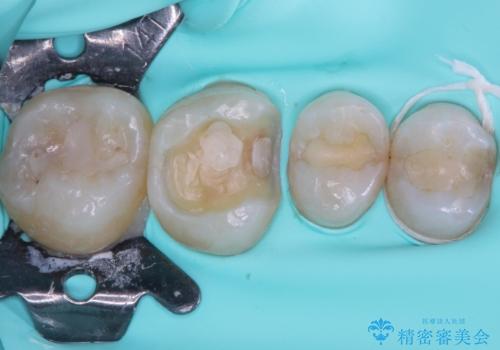

- 近医にて抜歯が必要と診断されたとのことで来院された患者様です。

術前の診査では、歯が破折している可能性が高いものの、確実に抜歯が必要と診断ができない状態でした。

状況次第では抜歯が必要となり、その際にはインプラント治療を行うことを了承いただいた上で、破折していない場合には根管治療を行うこととしました。

土台の材料を外して顕微鏡下で確認したところ、歯根にまで及ぶ破折が認められたため、インプラント治療を行うこととしました。